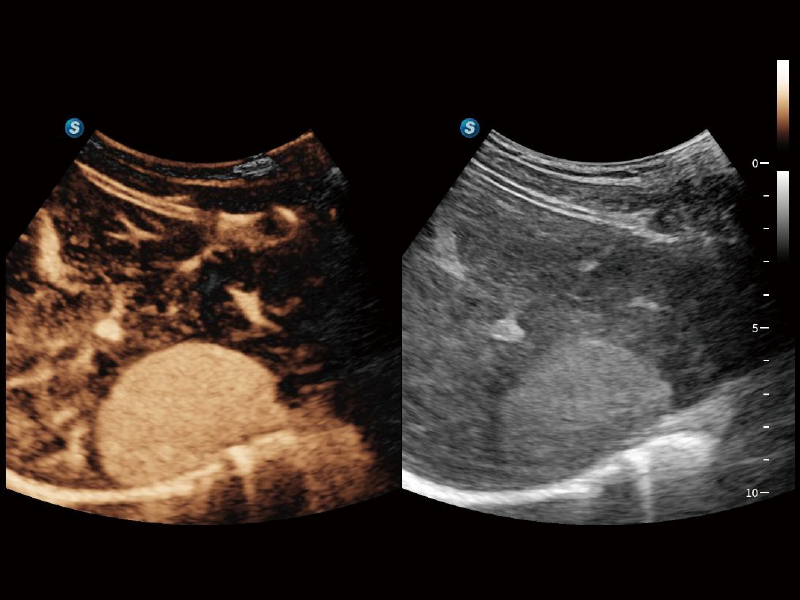

通過光照模型,使二維血流顯示出立體的效果,增加血流的敏感性、成束性,減少外溢??梢院推渌煌难骷夹g(shù)聯(lián)合使用,融合不同技術(shù)的優(yōu)勢(shì)。輕松應(yīng)對(duì)微小血管,增強(qiáng)血流的立體效果,提升視覺敏感性。

通過創(chuàng)新的Matrix E自適應(yīng)濾波算法,能有效濾除軟組織和噪聲信號(hào),最大限度保留超低速微細(xì)血流的信號(hào);結(jié)合超長(zhǎng)時(shí)間域算法,極大提升細(xì)微血流的敏感性和空間分辨率,更真實(shí)的反應(yīng)組織、包塊的血流灌注情況。